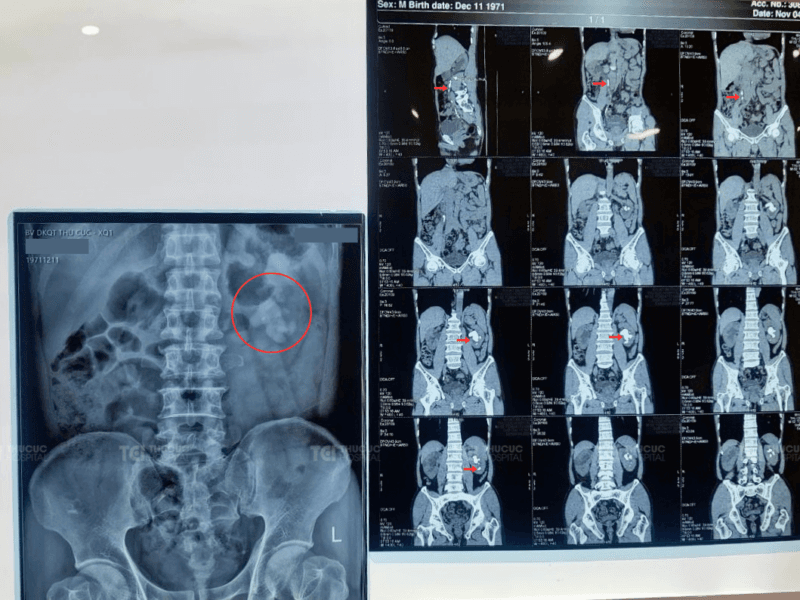

Ông P. nhập viện với biểu hiện đau hông lưng phải nghi ngờ do sỏi thận phải. Thế nhưng kết quả chẩn đoán cho thấy tình trạng nghiêm trọng hơn. Thận phải ứ nước độ II, nhiều viên sỏi rải rác khắp niệu quản, trong đó viên lớn nhất kích thước 15x5mm cùng các sỏi nhỏ khác ở thận.

Đặc biệt, thận trái của ông P. còn xuất hiện viên sỏi san hô lớn 38x29mm tại bể thận, kèm nhiều viên sỏi nhóm đài thận kích thước 13x7mm. Tình trạng này khiến đài bể thận trái giãn tới 13mm.

Phim chụp cho thấy sỏi nằm ở cả hai bên thận và niệu quản (Ảnh: TCI).